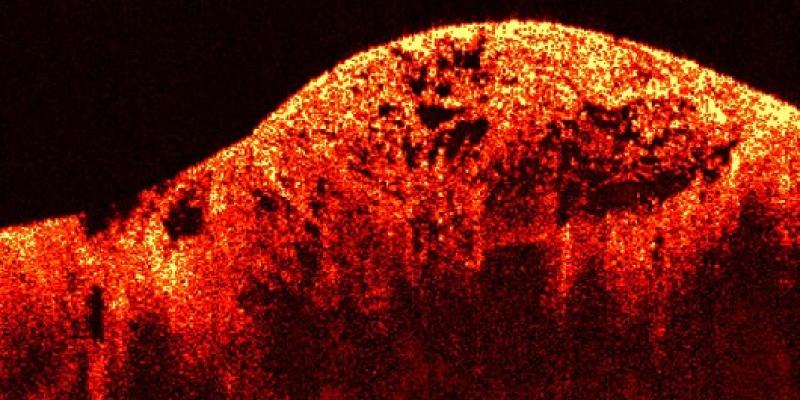

En definitiva, son un tipo de cáncer que se origina en los tejidos blandos (músculos, grasa, vasos sanguíneos, nervios, tendones, ligamentos y otros tejidos conectivos) o en los huesos. A diferencia de los carcinomas (que se originan en células que recubren órganos o glándulas, como la piel o el revestimiento intestinal), los sarcomas son de origen mesenquimal.

• De tejidos blandos: Liposarcoma (en el tejido graso), leiomiosarcoma (en el músculo liso), angiosarcoma (en los vasos sanguíneos), sarcoma sinovial, histiocitoma fibroso maligno (ahora más conocido como sarcoma pleomórfico indiferenciado), entre otros. Pueden aparecer en cualquier parte del cuerpo, aunque son más comunes en las extremidades, el tronco y el retroperitoneo (detrás del abdomen).